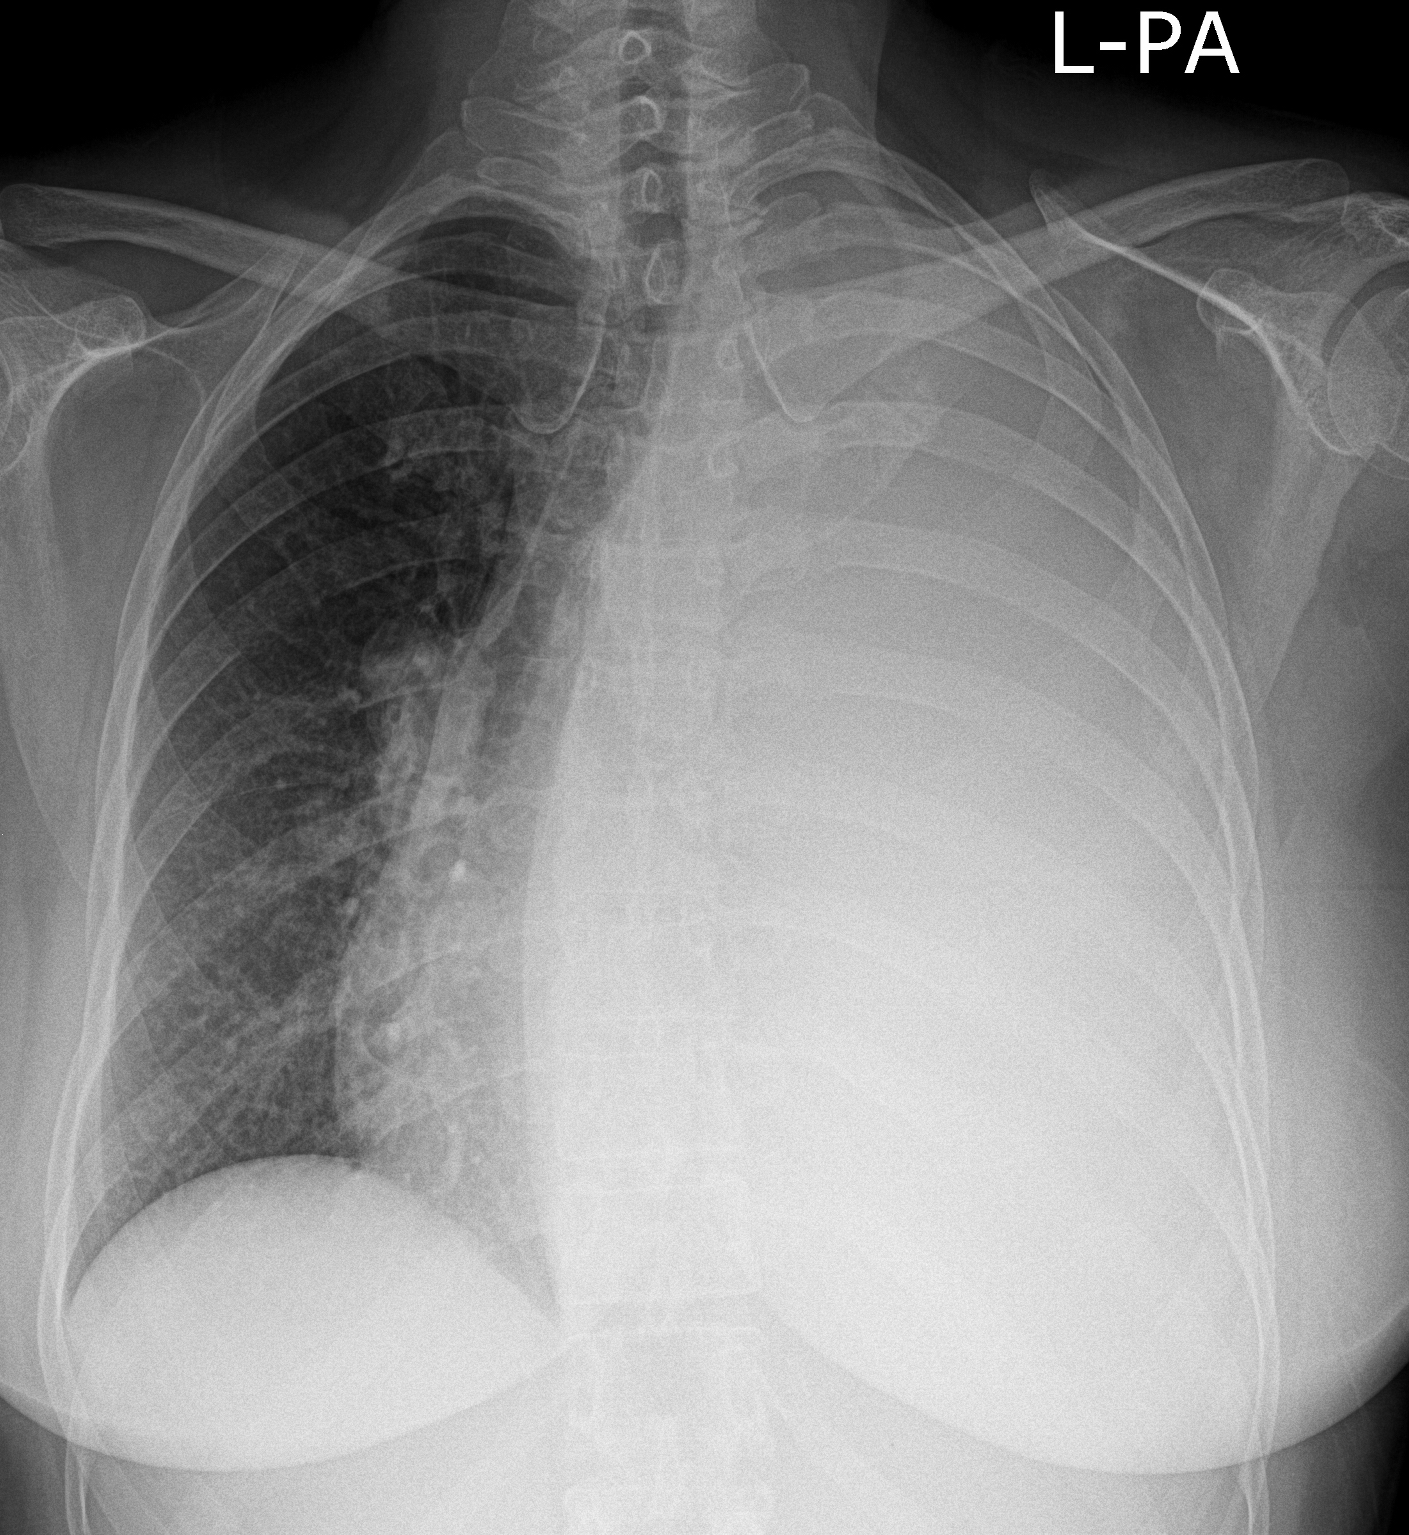

25. Massive pulmonary embolism. CT angiography (axial image and coronal reconstruction)

84 year old woman: dyspnea, elevated D-dimer.

Pulmonary embolism, riding embolus in the pulmonary trunk and in both pulmonary arteries + in smaller branches bilaterally as well. Contrast filling defects are seen according to the emboli.